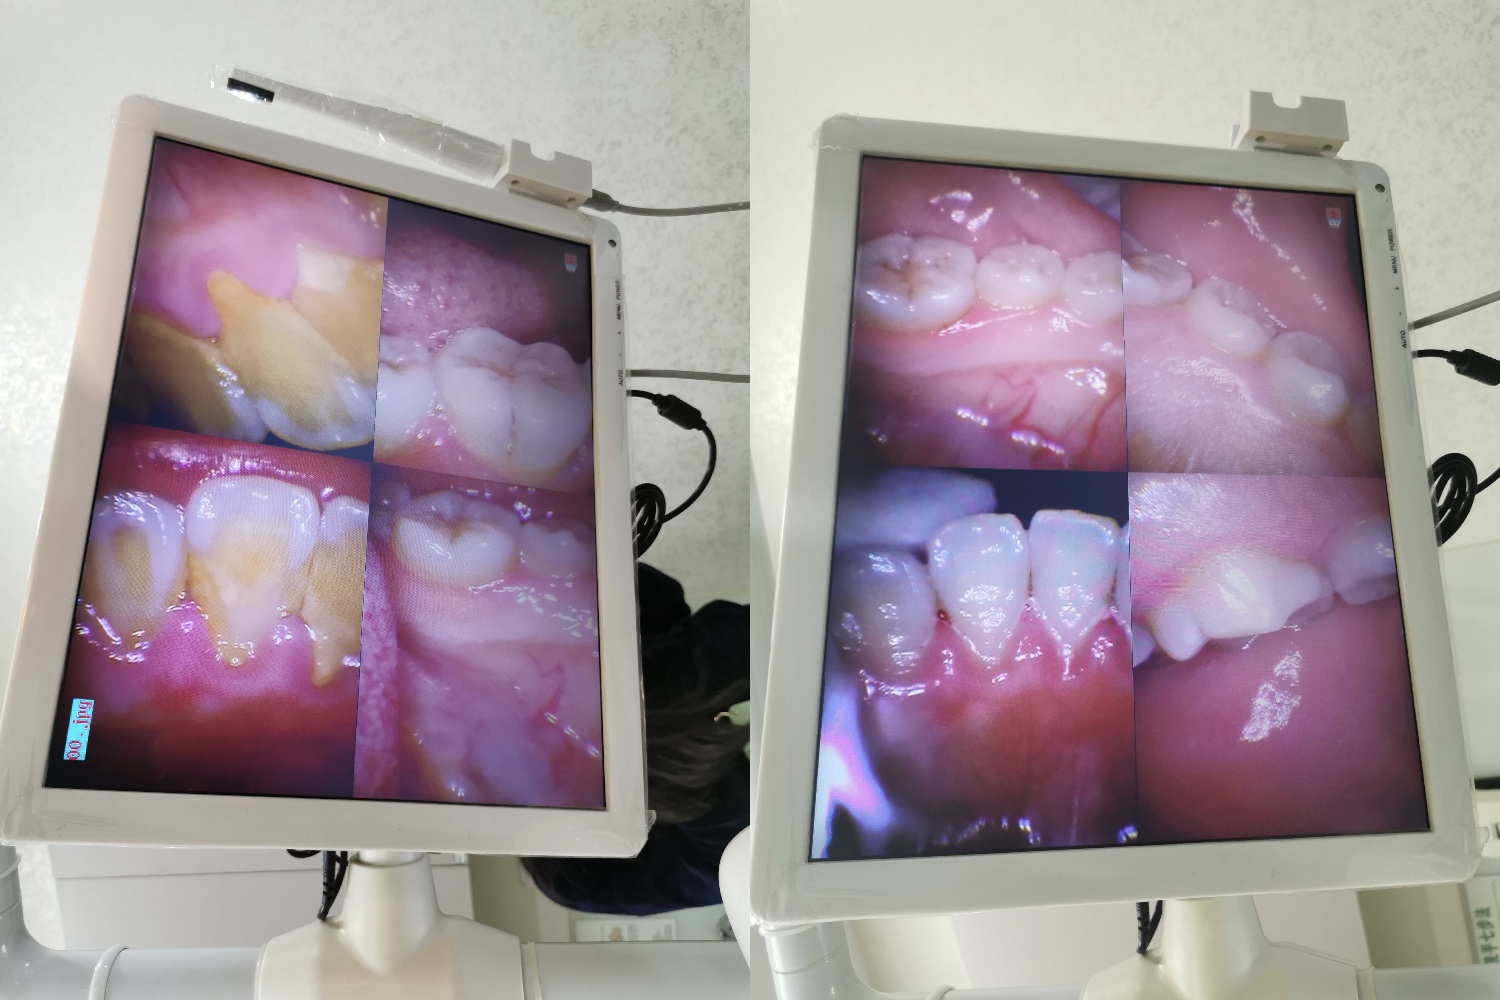

助理医生拍了几张牙结石照片给我看,咦~这厚厚的黄色的牙结石,真的是自己的吗?不敢相信呢!这时,助理医生从器械那里拿了一根管子,她告诉我这是吸口水的管子,因为在操作过程中,可能会产生口水,管子是一次性的,工具也消过毒。看到医生们都如此温柔细心,自己丝毫不担心会不卫生甚至感染的问题。我配合医生戴上防光眼罩,静静地躺下去,等待洗牙带来的“第一阵痛”。

但真正开始洗的时候,一点痛感都没有,于是我很快就适应了,只听见“呲呲呲”的声音,全程都没有出现痛感,只是张嘴张的有点累。不过幻想着牙结石正在一点一点被消灭,张个嘴又算什么呢。尤其是洗完牙、抛了光之后,看到牙齿的前后对比,一个原本被黄色牙结石紧紧包围的牙齿,瞬间被脱去了黄色外套,露出了牙齿本来的面目,心中的满足感油然而生。